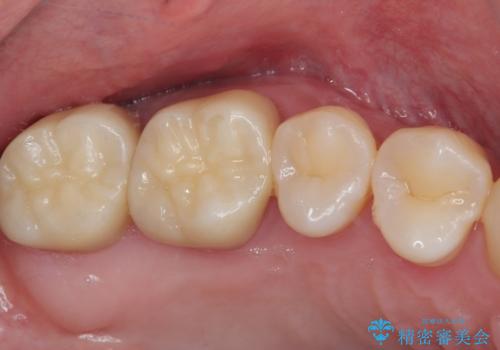

まずはしみる上顎の歯を仮歯に置き換え、その後下顎の根管治療を行った上で、異常が認められなければオールセラミッククラウンにて補綴治療を行うこととしました。

上顎は仮歯に置き換えた後に、それまでの痛みは一切感じなくなり、下顎も一度目の根管治療で痛みを感じることはなくなりました。

根管治療を行った歯の周辺にある病変は数ヶ月後にレントゲン写真を撮って確認する必要があるため、今後経過観察を行っていく予定です。